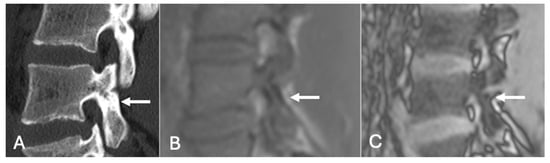

Figure 19.

Pars defect assessment CT image (A) and chemical shift in-phase (B) and out-of-phase (C), showing pars defect of L5 (arrow).

Figure 20.

Pars defect assessment sagittal CT image (A) and chemical shift in-phase (B) and out-of-phase (C), showing intact pars of L4 (arrow).

Figure 21. Focal marrow hyperplasia in L4. Sagittal T1 (A), T2 (B), CT (C), and chemical shift (D,E), showing heterogeneous signal on T1 and T2 and sclerosis on CT with significant signal drop on chemical shift images (D,E). - Characterising Indeterminate Marrow Lesions: In patients with cancer, incidental marrow lesions often cause clinical concern. CSI helps identify those lesions with retained fat, reducing the need for biopsy or further imaging such as bone scan or positron emission tomography (PET) [39] (Figure 18).

- On a slightly different theme, whilst not strictly utilising the SI drop-off calculations, chemical shift imaging in itself has been demonstrated to assess for and evaluate pars defects. In a cohort of 70 patients, chemical shift MRI effectively identified both intact and defective pars interarticularies, with out-of-phase imaging slightly better for detecting defects and in-phase imaging better for confirming intact pars. Although differences were not statistically significant, the technique demonstrated strong intra- and interobserver reliability and offers a fast, reliable complement to conventional MRI [41] (Figure 19 and Figure 20).